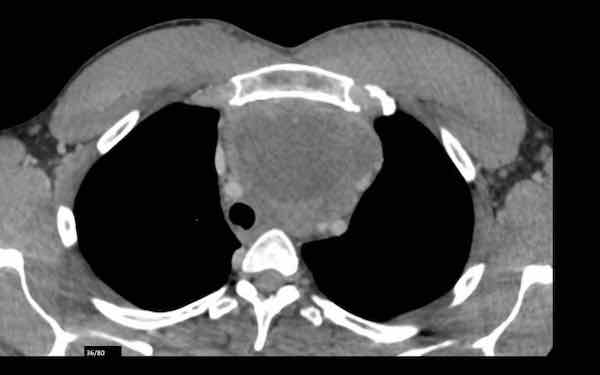

Đây là hình ảnh của một nam giới 24 tuổi.

Hãy quan sát kỹ các hình ảnh trước.

Câu hỏi: đây có phải là tuyến ức bình thường không?

Hình ảnh

Mặc dù tuyến ức này khá lớn, nhưng có hình tam giác bình thường và chứa mỡ (mũi tên).

Đây là tuyến ức bình thường.